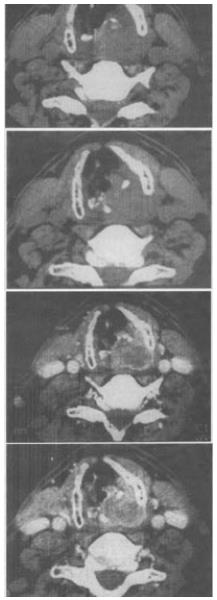

- 单项选择题 男性,60岁。声音嘶哑2个月余,无其他不适。根据给出的CT图像,应拟诊为()。

- D